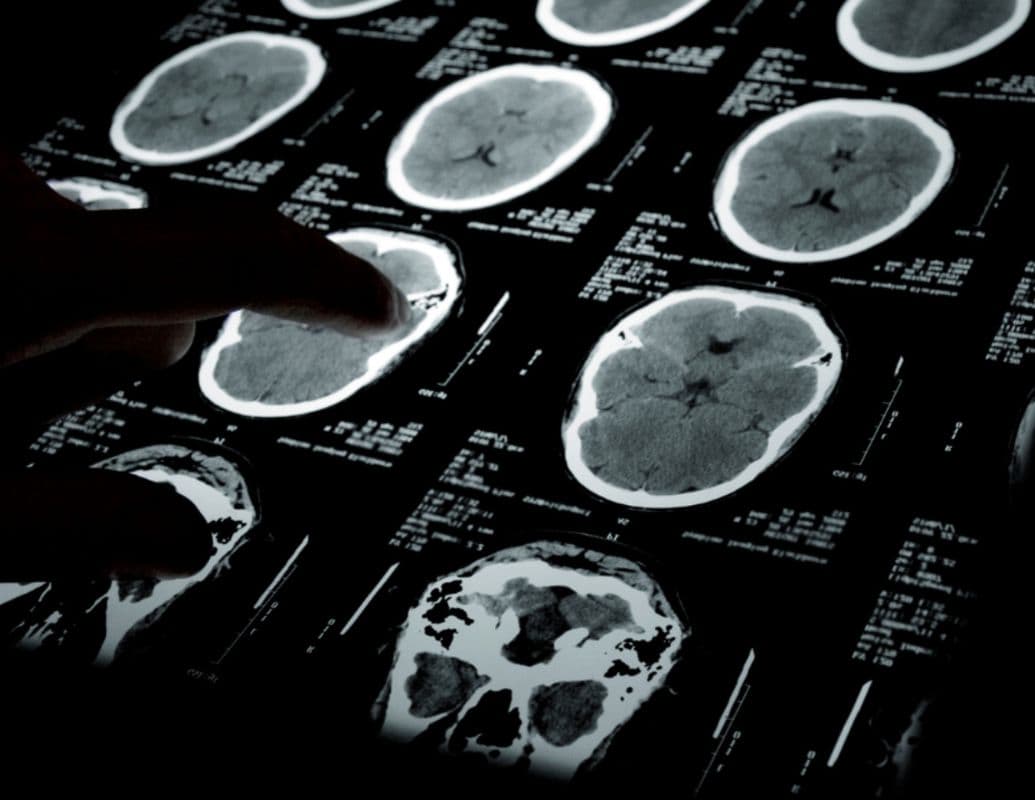

Creatine increases brain phosphocreatine and supports ATP recycling, so neurons recover faster after bursts of activity and stress. Human imaging and biochemical studies 2 confirm that supplementing with creatine raises brain creatine stores, which correlates with better processing speed and attention in some trials.

Acute studies 3 also show benefit: a single oral dose improved cognitive processing speed and maintained high-energy phosphate levels during sleep deprivation, suggesting creatine helps the brain resist temporary energy shortfalls. It inhibits a reduction in pH and alters PCr/Pi, ATP, and tCr/tNAA.

Researchers hypothesize that creatine’s energy-support role could slow neurodegenerative processes; preliminary human trials now test that idea. A recent feasibility trial 5 in people with Alzheimer’s disease showed oral creatine raised brain total creatine by ~11% after weeks of supplementation. It produced small but statistically significant gains on composite cognitive tests (global and fluid cognition), suggesting potential for further study.